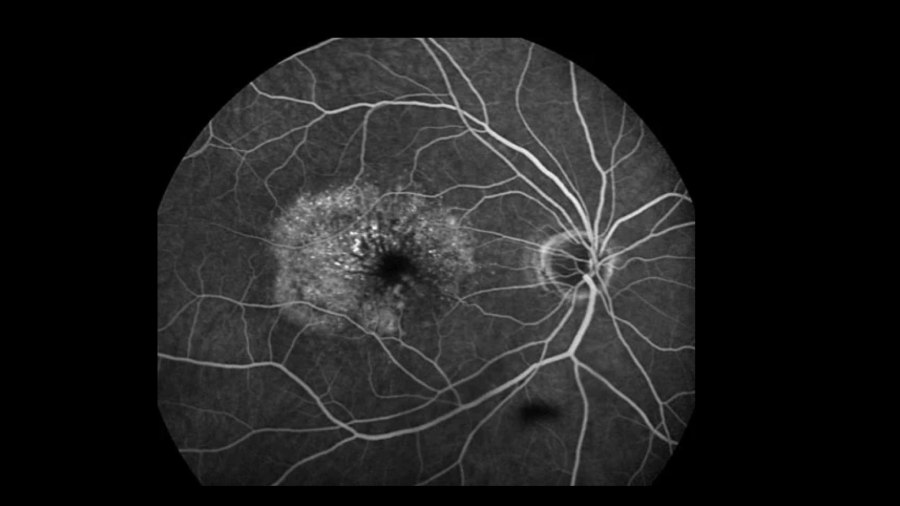

- Ophtalmologie : René Fritsch